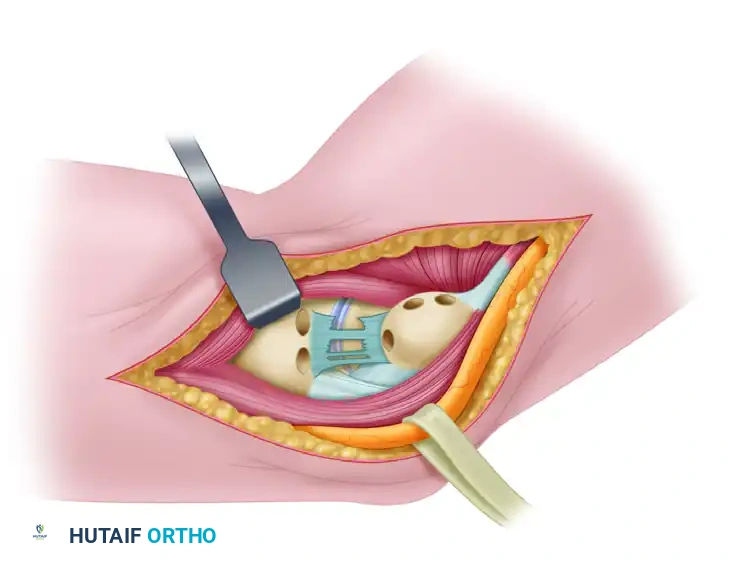

FIGURE 47-51: Jobe ulnar collateral ligament reconstruction. Medial aspect of right elbow before reconstruction showing remnant of ulnar collateral ligament and proper placement of bone tunnels in ulna and medial humeral condyle. Holes are drilled in ulna 5 mm from joint. Ulnar tunnel and closed-end tunnel in medial epicondyle are centered over bony attachments of ligament.